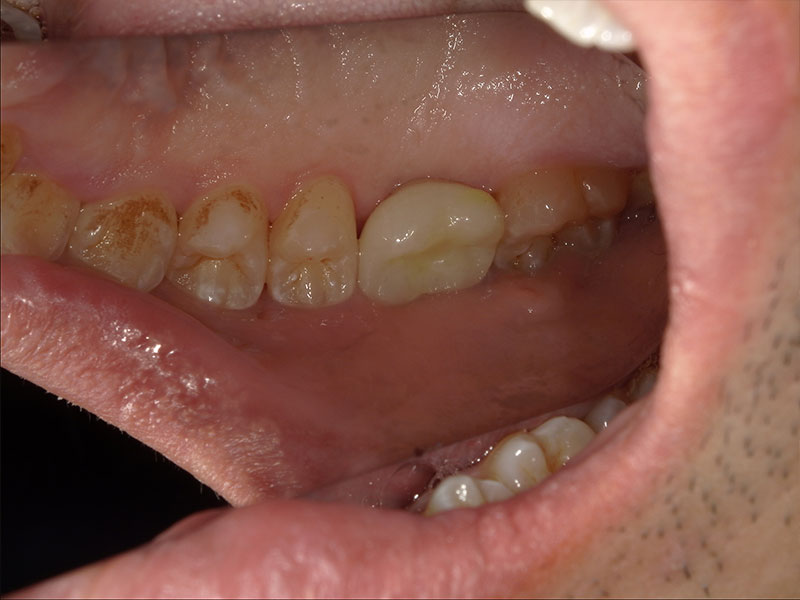

患者様は66歳、女性の方で、主訴としては右下の奥歯の治療をしたいとのことで来院されました。元々の当院に来院されたきっかけとしては、元々他院に行かれていたのですが、左右両側の親知らずの周囲の歯茎が炎症を起こし痛みを繰り返していたのですが、過去に顎が外れたことがあるらしく、そこから怖くて大きくお口を開けれないとのことでした。お口が開きにくいことから抜歯が困難とのことで他院ドクターからそのまま患部の洗浄をしながらの様子見でずっと過ごされていたとのことです。そこで当院に来院していただいてお口を見させていただいたのですが、意外とお口を開けていただくことができたので、親知らずの根っこの形態や生え方など総合的に考慮して、器具さえ入れば抜歯できると考え当院で抜歯させていただきました。抜歯の際は顎が外れないように患者様自身の手で少し押さえてもらいながら行いました。初めはとても不安そうだったのですが、案外すんなりと抜歯できたのでよかったです。そこから安心していただいたのか残りの反対の方の親知らずも抜歯しました。そして最終的には右下のインプラント治療を任せてもらうことになりました。

右下6の状態としては虫歯が進行していて、保存不可の状態でした。患者様との相談の結果、インプラント治療を行うことになりました。